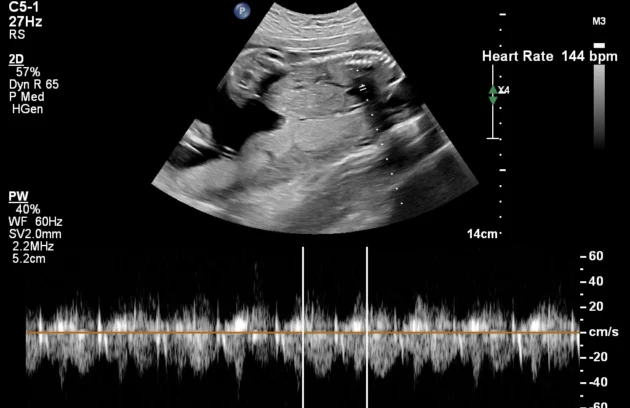

🔹 Fetal Echo / Adult Echo (Echocardiography)

Echo (Echocardiography) is a specialized ultrasound used to examine the heart. Fetal Echo evaluates the baby’s heart structure and function during pregnancy, while Adult Echo checks heart health in adults. It helps detect congenital heart defects, valve problems, and blood flow issues. If you need a fetal echo in Kathmandu, this test plays a vital role in early diagnosis and treatment planning.